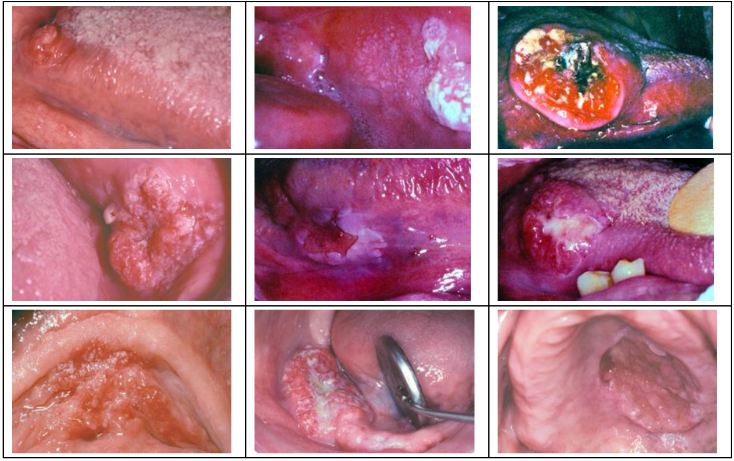

| papilloma (6, 11) |

30~50y | 軟顎、口腔常見 | 單發、低傳染 | |||

pedunculated, sessile(少)  |

| Verruca vulgaris 尋常疣 (2, 4) |

- | 皮膚、口腔(少見、接觸、自傳染) | 大多是sessile(無梗) | |||

| Condyloma acuminatum 尖銳濕疣 |

多顆、界線清楚、無痛、兒童有機會自愈 | |||

廣底、papillary 突起不明顯、Koilocytes (空亮、葡萄乾核)  |

| Multifocal epithelial hyperplasia (Heck’s disease, 13, 32) |

低社經、HIV | 唇、頰、舌 | 小、軟、多、無痛 | |||

Papillomatous variant

Papulonodular

Verrucous Carcinoma(VC)

- Ackerman’s tumor

- 分化良好,不會鑽,用推的(Pushing) → 侵犯稍差

- HPV 低相關

- 四周可能有 SCC(20%)